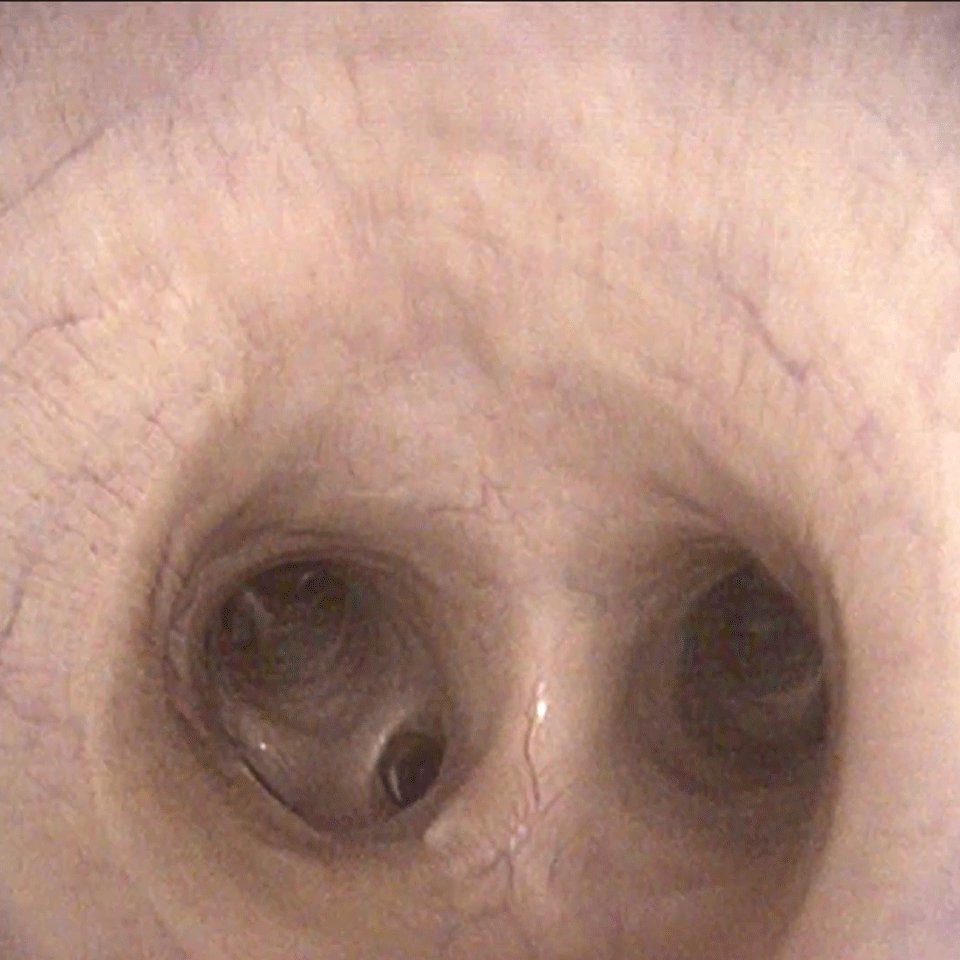

Hochgradige Schwellung der Bifurcatio Tracheae

Hochgradige Sekretansammlung in der Luftröhre